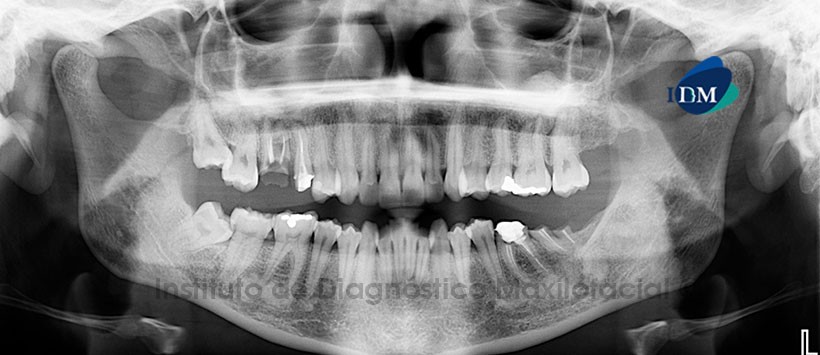

A la evaluación de la radiografía panorámica (Figura1) observamos múltiples zonas radiopacas de densidad ósea localizadas en ambos maxilares, con limites definidos, próximas a los ápices de las piezas comprometidas, en el caso del maxilar superior se proyectan en los senos maxilares.

Al estudio mediante tomografía computarizada de haz cónico (CBCT), mediante reformación panorámica (Figura 2), cortes axiales (Figura 3) y coronales (Figura 4) se evidencia alteración del patrón de trabeculado óseo de manera focalizada a nivel apical de las piezas 1.8, 1.7, 2.6, 2.7, 3.5, 3.6, 3.7, 3.8, 4.5, 4.6 y 4.7. Presenta una densidad aumentada compatible con hueso y/o cemento.

Conclusión: Imágenes sugerentes de Displasia Cemento ósea Florida.